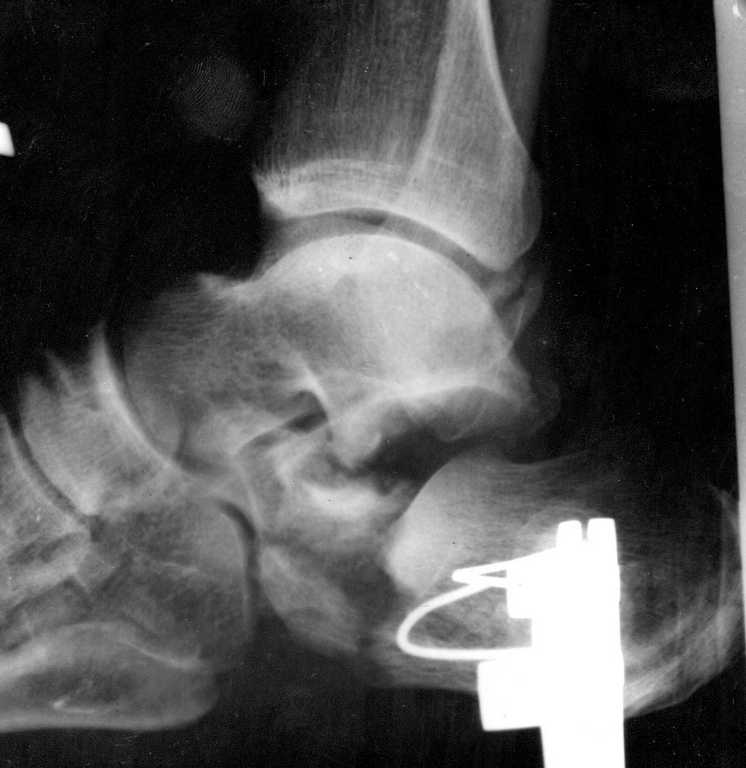

задняя фасетка выглядит более-менее целой, передняя - оскольчатая (конечно нужны доп проекции). Если пациент не действующий олимпийский чемпион, ограничился бы репозицией по Essex-Lopresti (перелом похоже начинался как "с языковидным фрвгментом"), возможно с фиксацией винтами через проколы. Очень вероятно, что дело закончится артродезом. но можно сохранить пяточные углы без высокого риска осложнений. Дешево и сердито.

Перелом типа "утиного клюва" как и указано ранее,наименее инвазивно - ввести винт Шанца в основной фрагмент, под ЭОП контролем репонировать к суставной тарана с восстановлением формы пятки и всех углов и фиксировать - можно спицы, можно винты канблированные. Если же сроки более нескольких дней - то придется видимо открываться.

Приветствую,коллеги!Извините,но немного непонятно , как можно советовать, основываясь на только одной проекции. Извините, но необходимы, как минимум, аксильная (Харриса) и косая (Бродена)проекции . Это даёт неоходимый минимум информации о степени разрушения подтаранного сустава. Хорошо бы так же иметь КТ и фото мягких тканей(внешний вид пятки). После этого стоит говорить о тактике лечения

Уважаемый Дмитрий! Абсолютно с Вами согласен, но думаю, что это уже частности необходимые для предоперационного планирования и зависят от мощности лечебного учереждения, чем и будет заниматься доктор непосредственно сам. Вопрос же принципиально заключается как оперировать? И мне кажется, что даже по этому малоинформативному снимку Вы представляете степень разрушения кости.